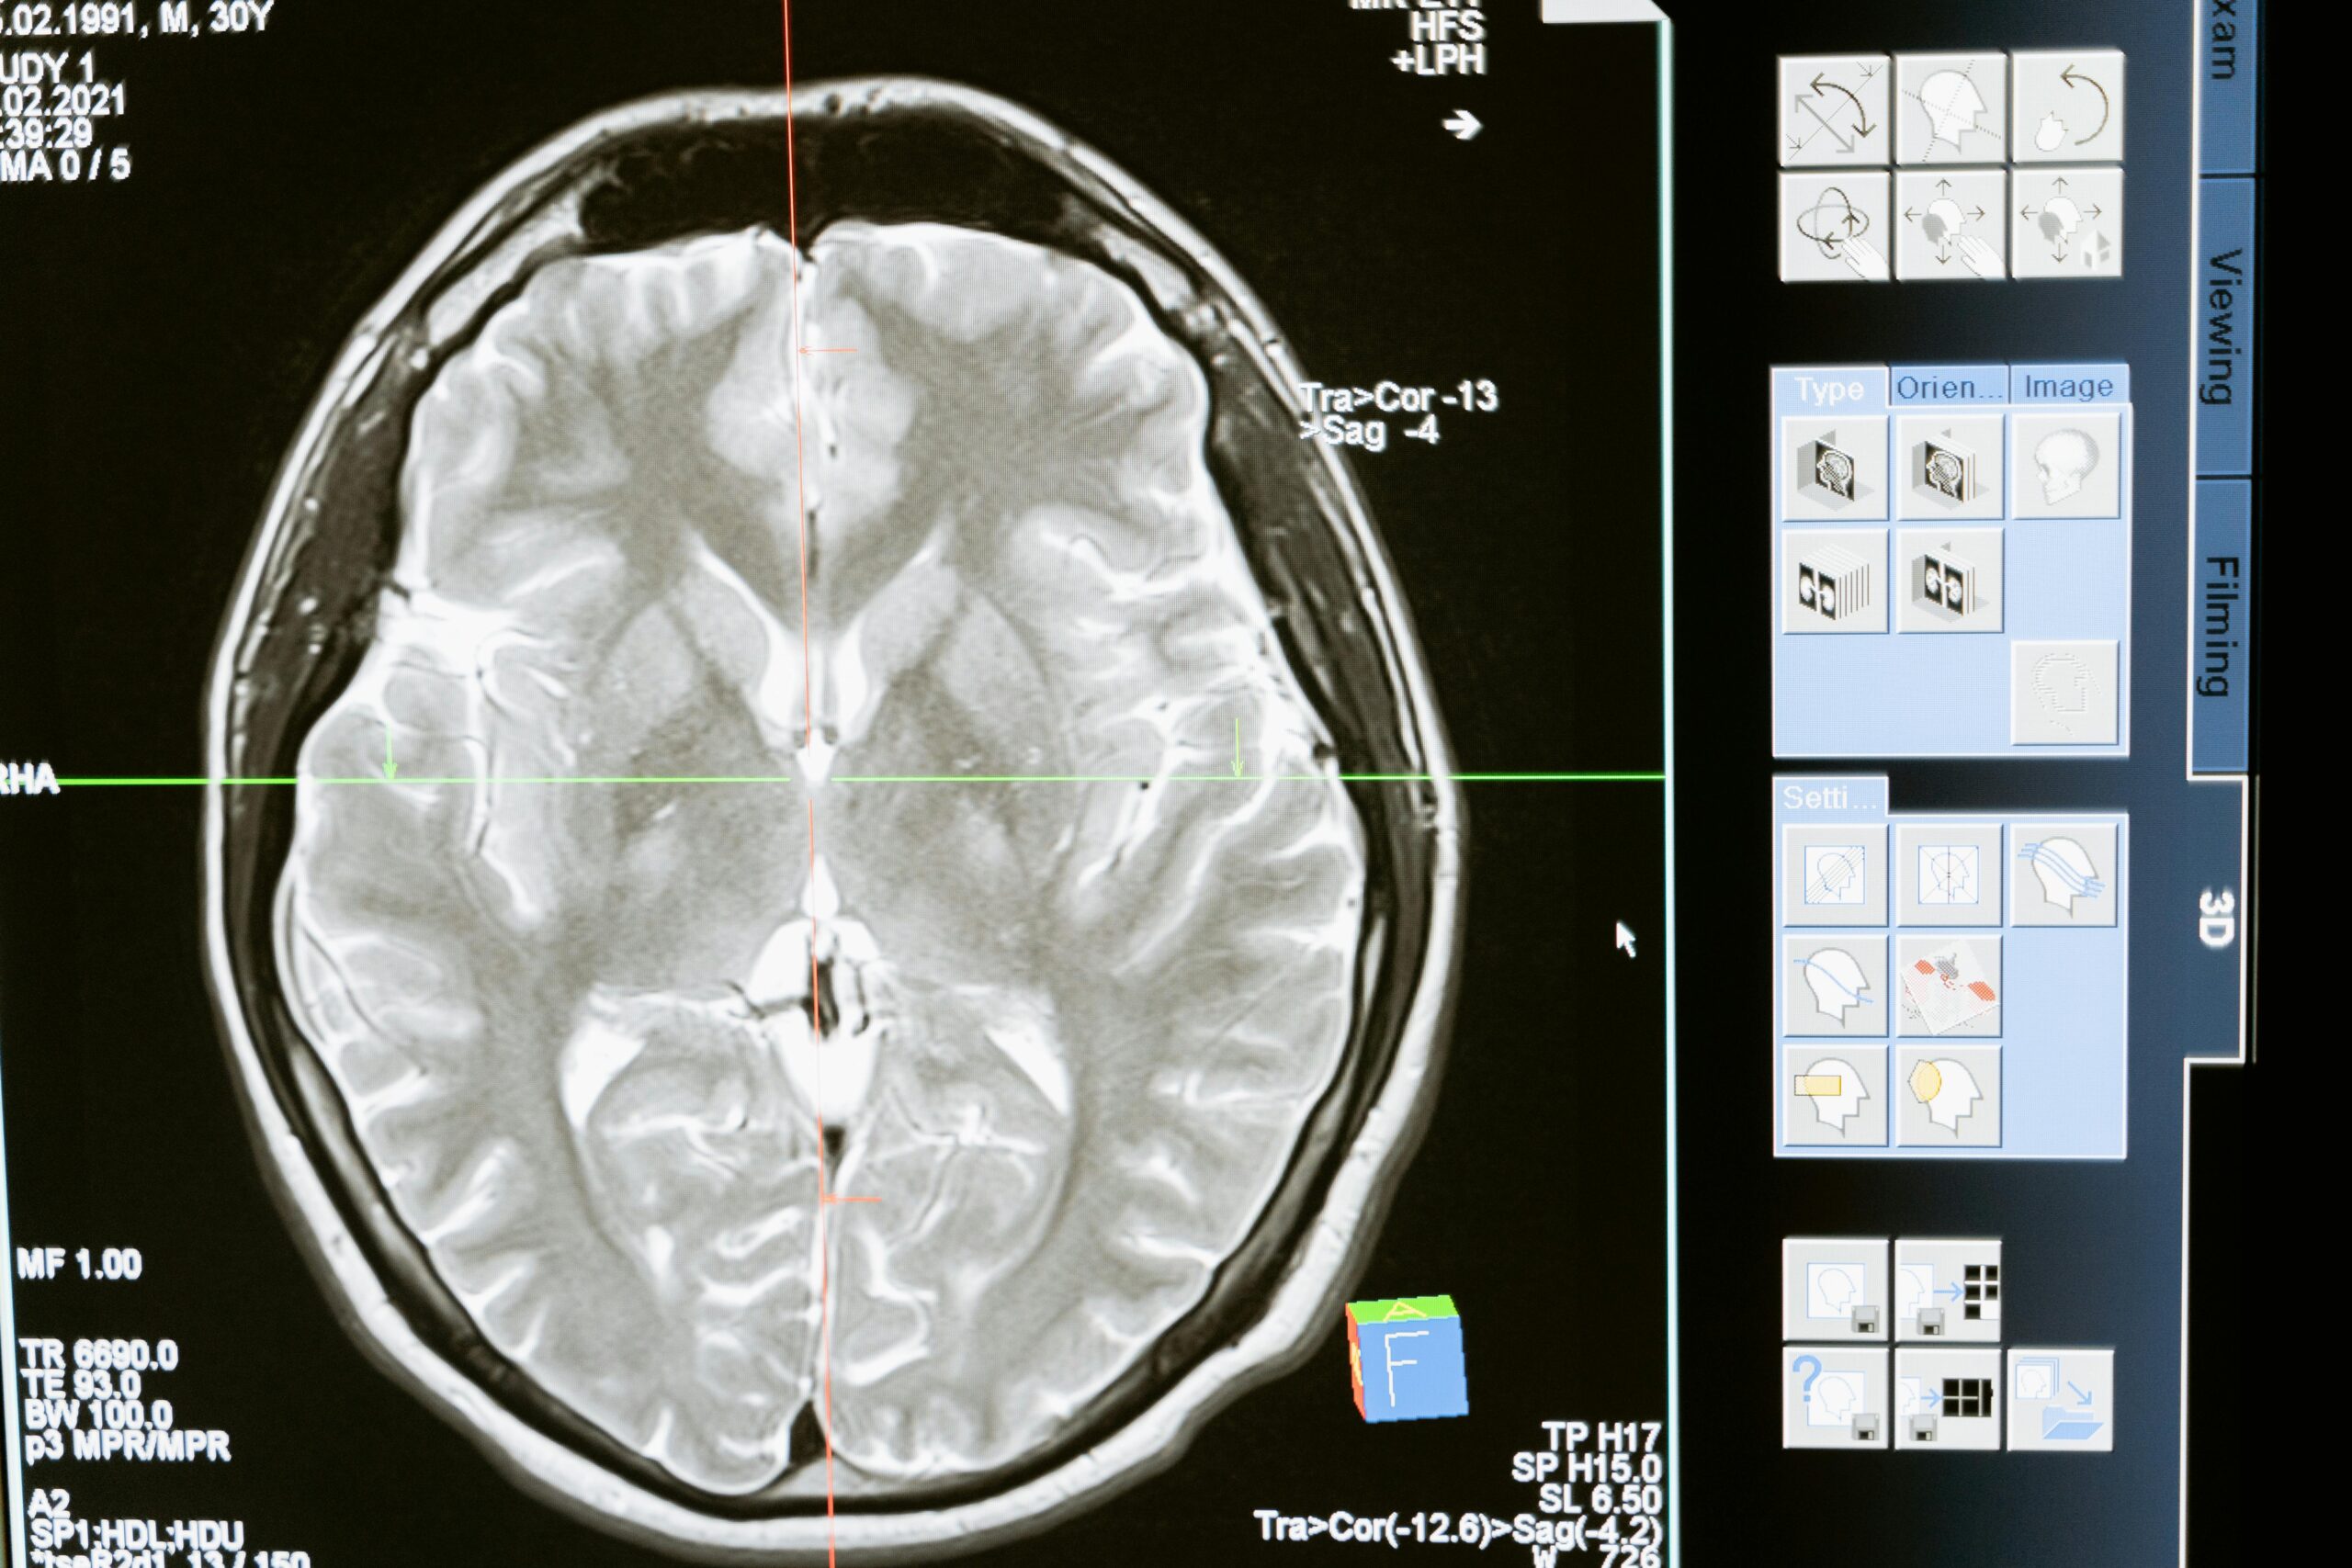

Diagnóstico

Para detectar un glioma, el especialista puede indicar:

Imágenes por resonancia magnética (convencional o funcional, perfusión, espectroscopia).